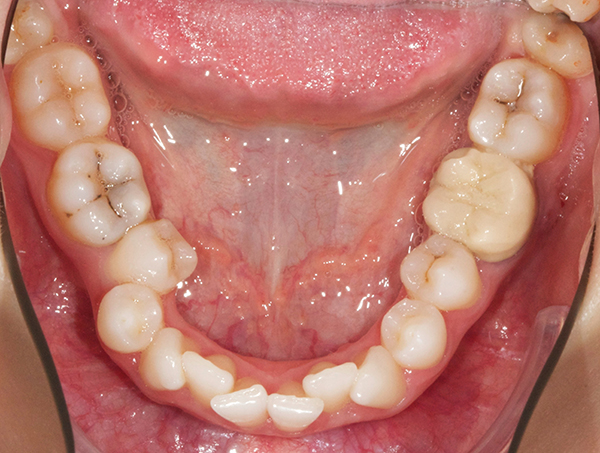

The interdisciplinary treatment plan to establish good oral health, esthetics, and function included prophylaxis and oral hygiene instructions as first steps. Respective teeth were extracted and orthodontic treatment was carried out. Figure 4 and Figure 5 depict the intraoral situation before orthodontic treatment with fixed appliances and ceramic brackets; Figure 6 through Figure 8 show the situation after orthodontic treatment, which lasted 18 months.

Fig 5. Preoperative intraoral occlusal views of the maxillary (Fig 4) and mandibular (Fig 5) arches.

Figure 5